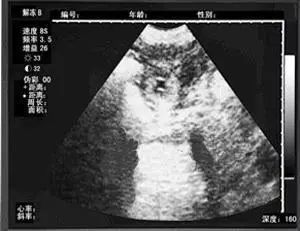

作为检验怀孕的重要依据,超声对人对猫都好使。猫咪进入孕期20天后,兽医就能通过超声波检测到胎儿的心跳,并大致判断数量。